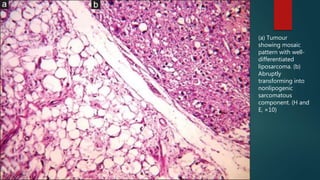

(a) Tumour

showing mosaic

pattern with well-

differentiated

liposarcoma. (b)

Abruptly

transforming into

nonlipogenic

sarcomatous

component. (H and

E, ×10)

(a) Tumour showing mosaic patternwith well- differentiated liposarcoma. (b) Abruptly transforming into nonlipogenic sarcomatous component. (H and E, ×10)